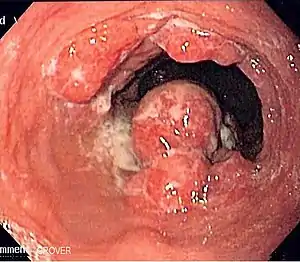

Although an occlusive tumor may be suspected on a barium swallow or barium meal, the diagnosis is best made with an examination using an endoscope. This involves the passing of a flexible tube with a light and camera down the esophagus and examining the wall, and is called an esophagogastroduodenoscopy. Biopsies taken of suspicious lesions are then examined histologically for signs of malignancy.

Endoscopic image of Barrett esophagus – a frequent precursor of esophageal adenocarcinoma